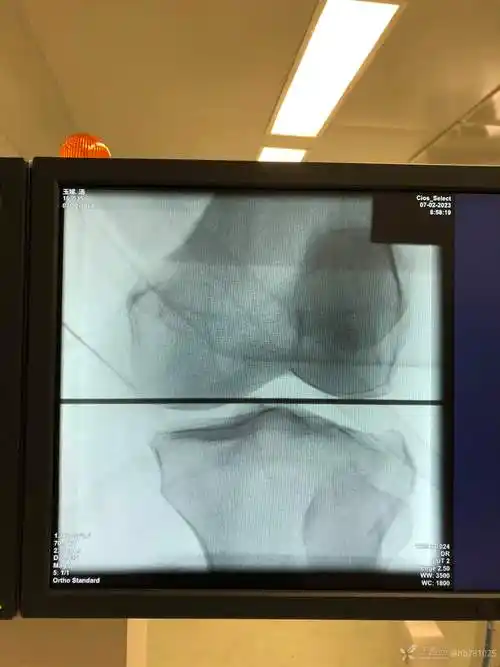

如何满意复位塌陷骨块胫骨平台骨折